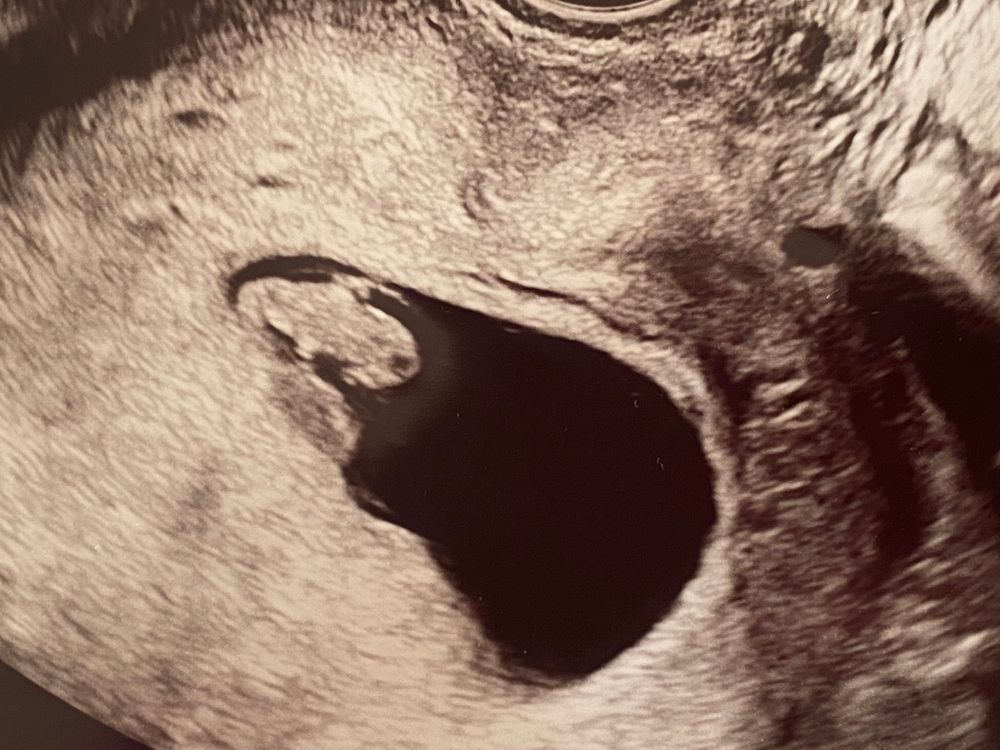

Лягушонок)))) поздравляю!

Лазерная эпиляция и беременость Размер ПЯ на 6 неделе